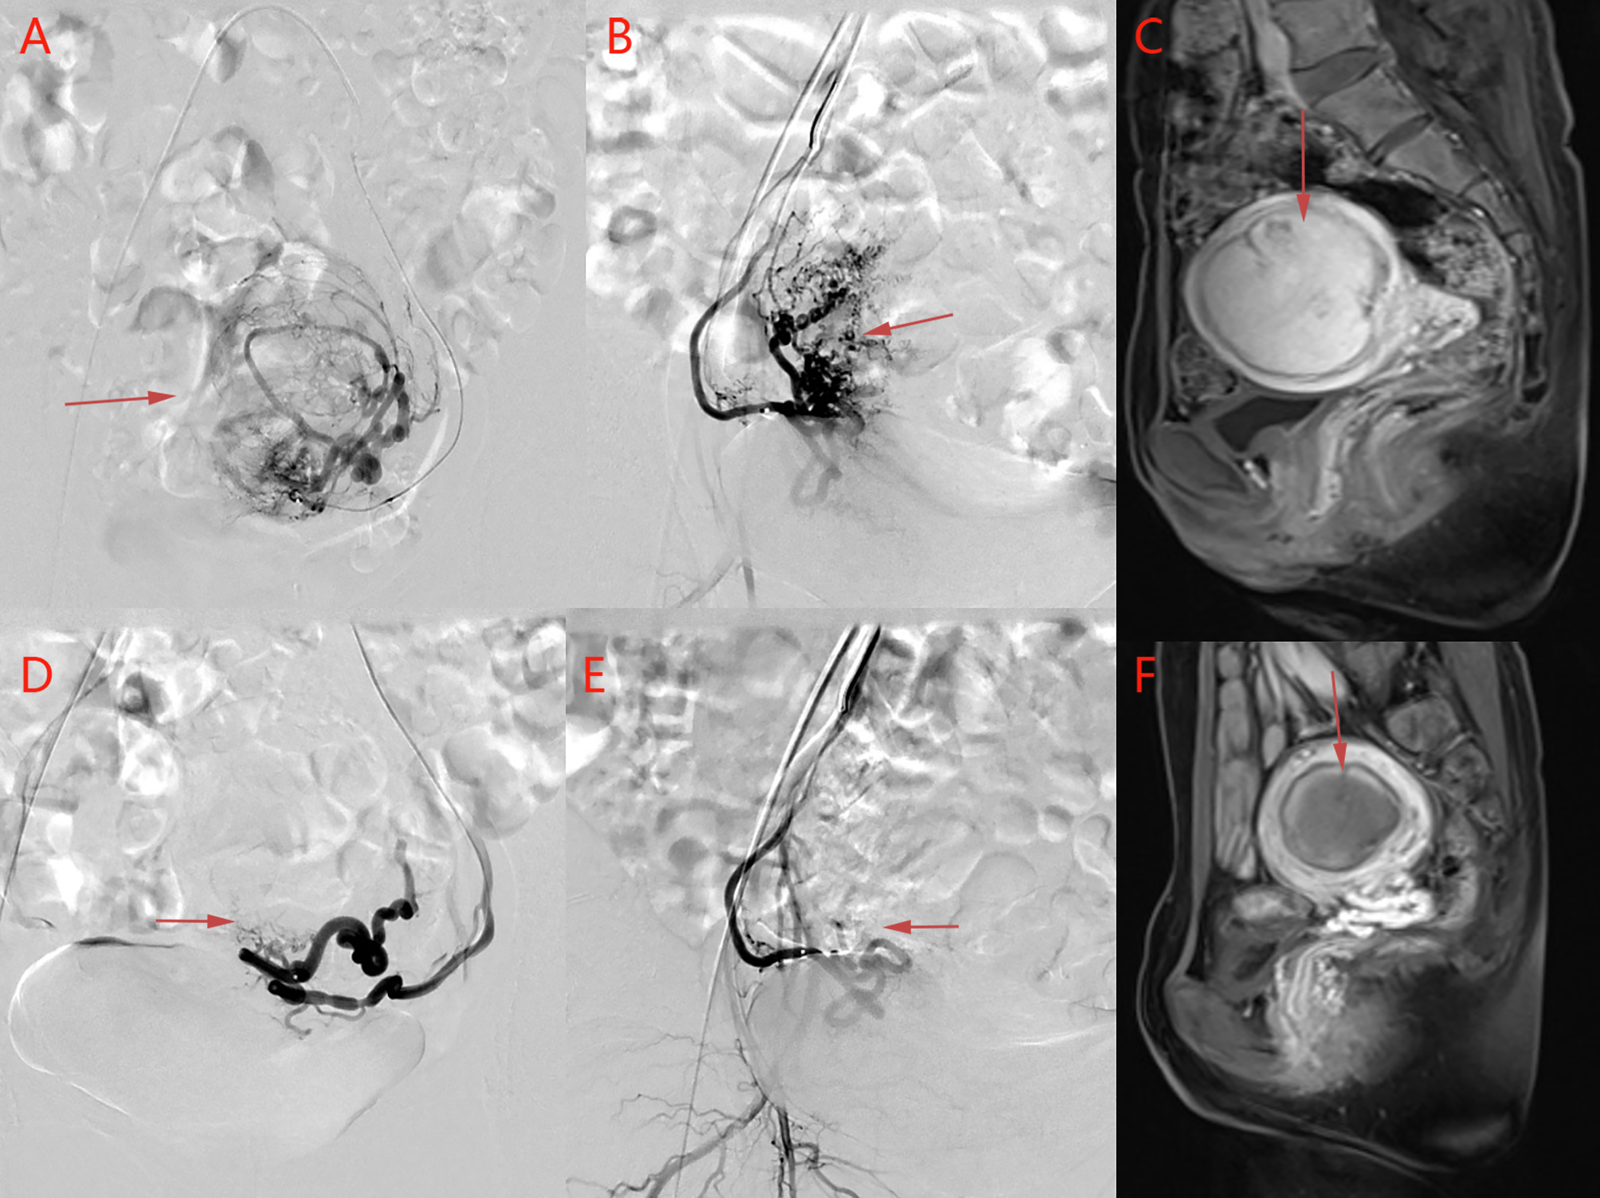

All patients underwent UAE successfully, and there were no significant differences in baseline data among the three groups (p > 0.05) (Table 1). There were no statistically significant differences in inflammatory indices among the three groups before embolization and 24 h after embolization (p > 0.05) (Table 2). MRI re-examination was performed 3 months after embolization and revealed that the uterine volumes and sizes of the leiomyomas in the three groups were significantly smaller than those before the embolization. The uterine volumes were reduced by approximately 53%, and there were no significant differences in the degree of change of the uterus and leiomyoma among the three groups (p > 0.05) (Table 3 and Figures 1A,D, 2C,F).

Figure 1

Images from a patient in the study group. (A) Before uterine artery embolization, and (D) after uterine artery embolization. The volume of uterine leiomyoma is reduced from 7.2 cm × 7.4 cm × 9.6 cm to 5.4 cm × 5.7 cm × 7.5 cm as revealed by pelvic MRI contrast, and the enhancement has disappeared. (B) Right uterine arteriography and (C) left uterine arteriography before uterine artery embolization. (E) Right uterine arteriography and (F) left uterine arteriography after uterine artery embolization. The bilateral leiomyoma arteries are basically occluded, and blood perfusion has disappeared completely after uterine artery embolization, suggesting the complete infarction of the myoma after uterine artery embolization.

Comparison of Uterine Artery Spasm During Surgery

Before embolization, uterine artery digital subtraction angiograms showed hypervascular uterine fibroids with dilated intramural arteries (Figures 1B,C, 2A,B). After UAE, the distal blood vessels were not evident, indicating successful embolization (Figures 1E,F, 2D,E). When embolic microspheres mixed with lidocaine were injected into the artery, obvious vasospasm was observed, resulting in an unclear development of the distal artery (Figure 3A,B).